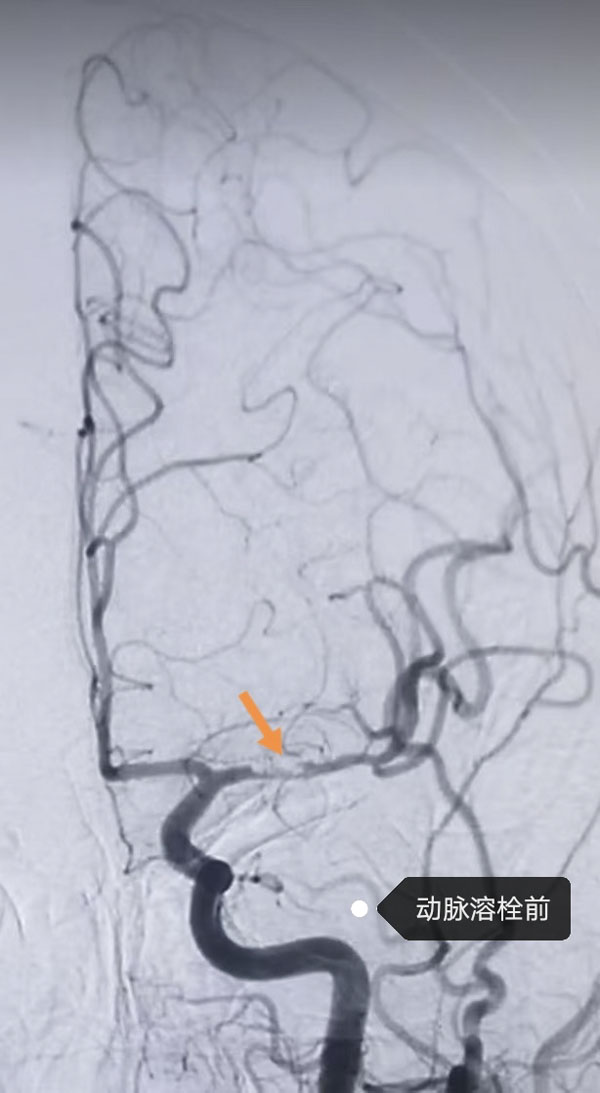

鑒于患者病情危急,接診醫生李晨曦緊急聯系介入組李彥青醫生啟動卒中救治流程,在介入手術室的人員的幫助下,為其實施腦動脈造影術。術中,李彥青發現患者此次發病的責任血管“左側大腦中動脈”雖存在血流再通,但局部仍為重度狹窄且血栓負荷重,遂決定通過左側頸內動脈給藥以改善局部血供。給藥后,復查造影顯示狹窄程度明顯改善。術后,患者NIHSS評分(神經功能缺損評分)由入院時的8分快速降至3分,言語及右側肢體活動不利明顯改善。一周后出院時,評分進一步降至1分,言語及肢體活動基本恢復正常。